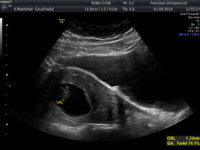

Anyway, all went perfect. Little bean kept hiding but we heard the heartbeat and were even allowed to record it. Images are all currently on a cd so can’t share those just yet but will once we have got them printed. Heartbeat was lovely and strong and dated are spot on

](*,)](/styles/default/xenforo/smilies/eusa_wall.gif) thank god i was in my own house but im sure the neighbours heard hahahaa. Tomorrow marks my 7week mark (although technically if i was to go by my scan i would only be 6+6) so i feel like thts a huge milestone for us right now. I cant wait to see our lil jellybean again on monday and see how much its has grown